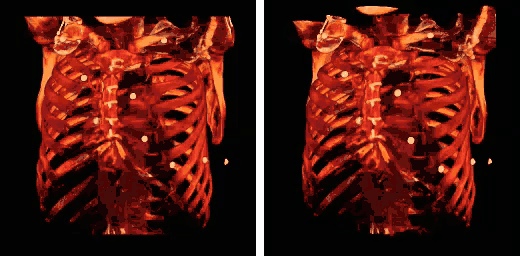

Rib fractures are the most common injury to the rib cage. These most frequently affect the middle ribs. When several adjacent ribs incur two or more fractures each, this can result in a flail chest which is a life-threatening condition.

Abnormalities of the rib cage include pectus excavatum ("sunken chest") and pectus carinatum ("pigeon chest"). A bifid rib is a bifurcated rib, split towards the sternal end, and usually just affecting one of the ribs of a pair. It is a congenital defect affecting about 1.2% of the population. It is often without symptoms though respiratory difficulties and other problems can arise.